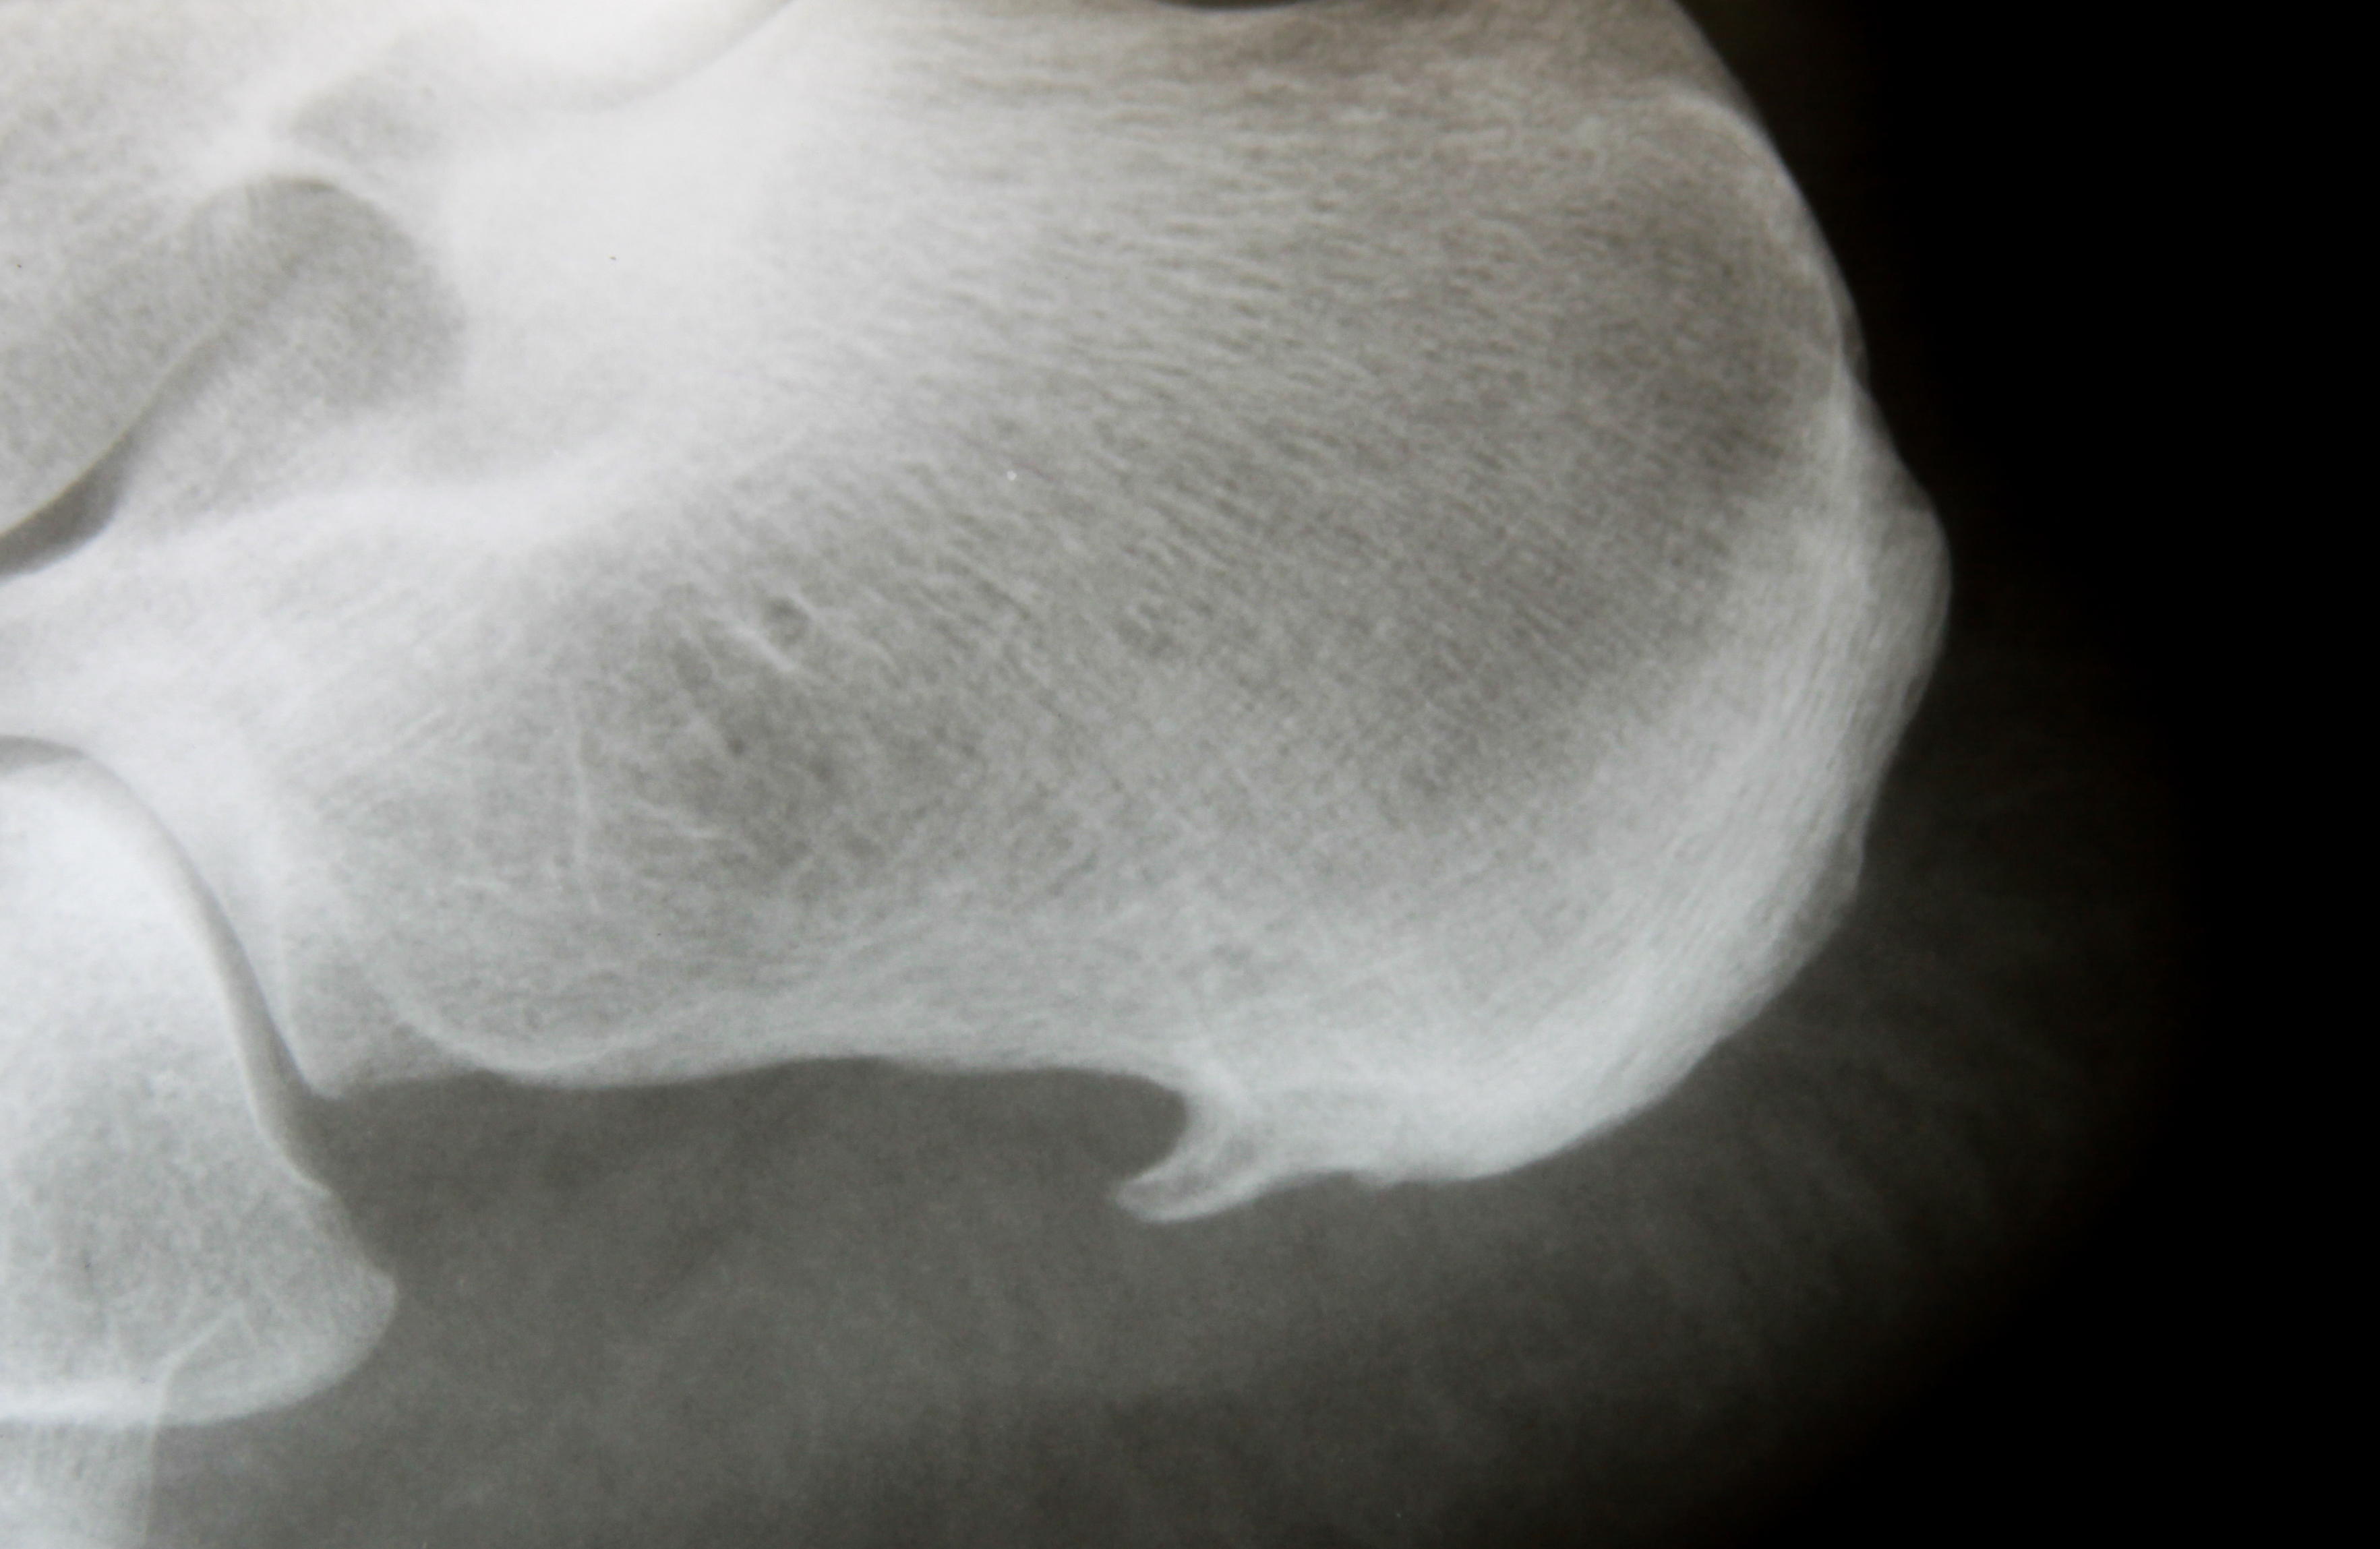

A heel spur or bone spur is a bony growth that pokes out from the bottom of your heel, where your heel bone connects to the ligament running between your heel and the ball of your foot (the plantar fascia). Heel spurs affect about 15% of people.

Heel spurs have been shown to develop in response to damage and strain to the soft tissues that insert at the bottom of the heel - in this case, the insertional fibres of the plantar fascia tissue. When the plantar fascia, which connects to the bottom of the heel bone, repetitively pulls on and places stress on the heel during movement, this creates micro-trauma. The body responds by trying to repair the area by creating more bone - this becomes the calcified protrusions that we know as heel spurs.

Due to the similarity in symptoms between a heel spur and other causes of heel pain like plantar fasciitis, confidently diagnosing a heel spur specifically includes taking your medical and injury history, a comprehensive clinical exam, and an x-ray.